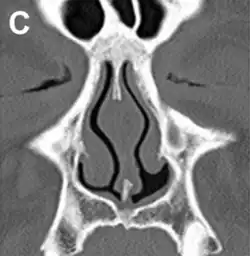

| ENS caused by loss of the inferior half of the left inferior turbinate. | |